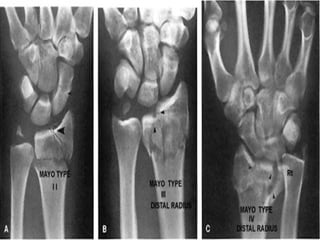

LOCALIZACION Diafisiaria Metafisiaria Epifisiaria Intraarticular Fractura-luxación

LOCALIZACION Diafisiaria MetafisiariaEpifisiaria Intraarticular Fractura-luxación